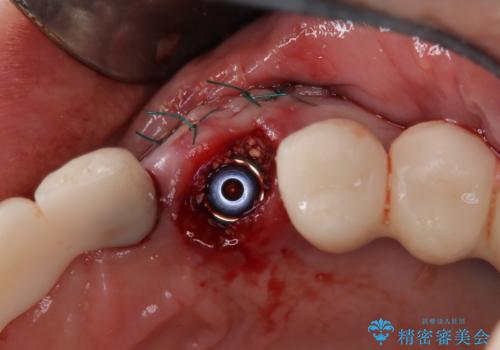

検査を行い、抜歯即時インプラント(1Dayインプラント)治療を行いました。

抜歯をしインプラント埋入と骨補填材を填入して仮歯までを1日で行う「抜歯即時埋入即時過重」の手術をし、3ヶ月後には、オールセラミックを被せて定期検診となりました。